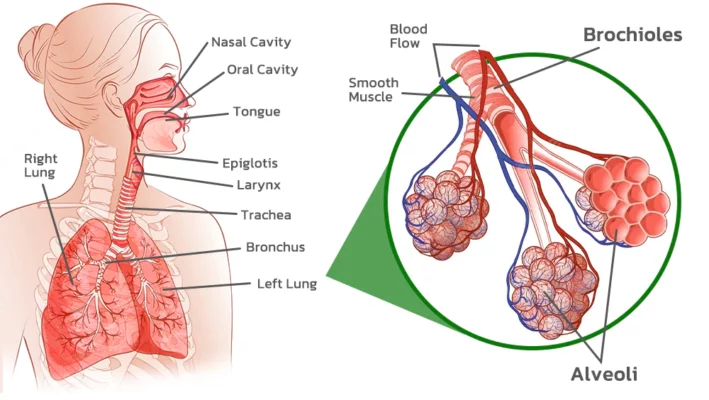

FastClean Cleaning Lung Herbal Extracts Ring is an inhaler that is used by inhaling through the nose. The herbal extracts are then absorbed through the trachea and into the lungs. The active ingredients work to dilute the mucus in the trachea and lungs, making it easier to expel phlegm and other waste materials from the respiratory system. This process helps to cleanse the lungs and upper airways and can lead to improved respiratory function and overall health.